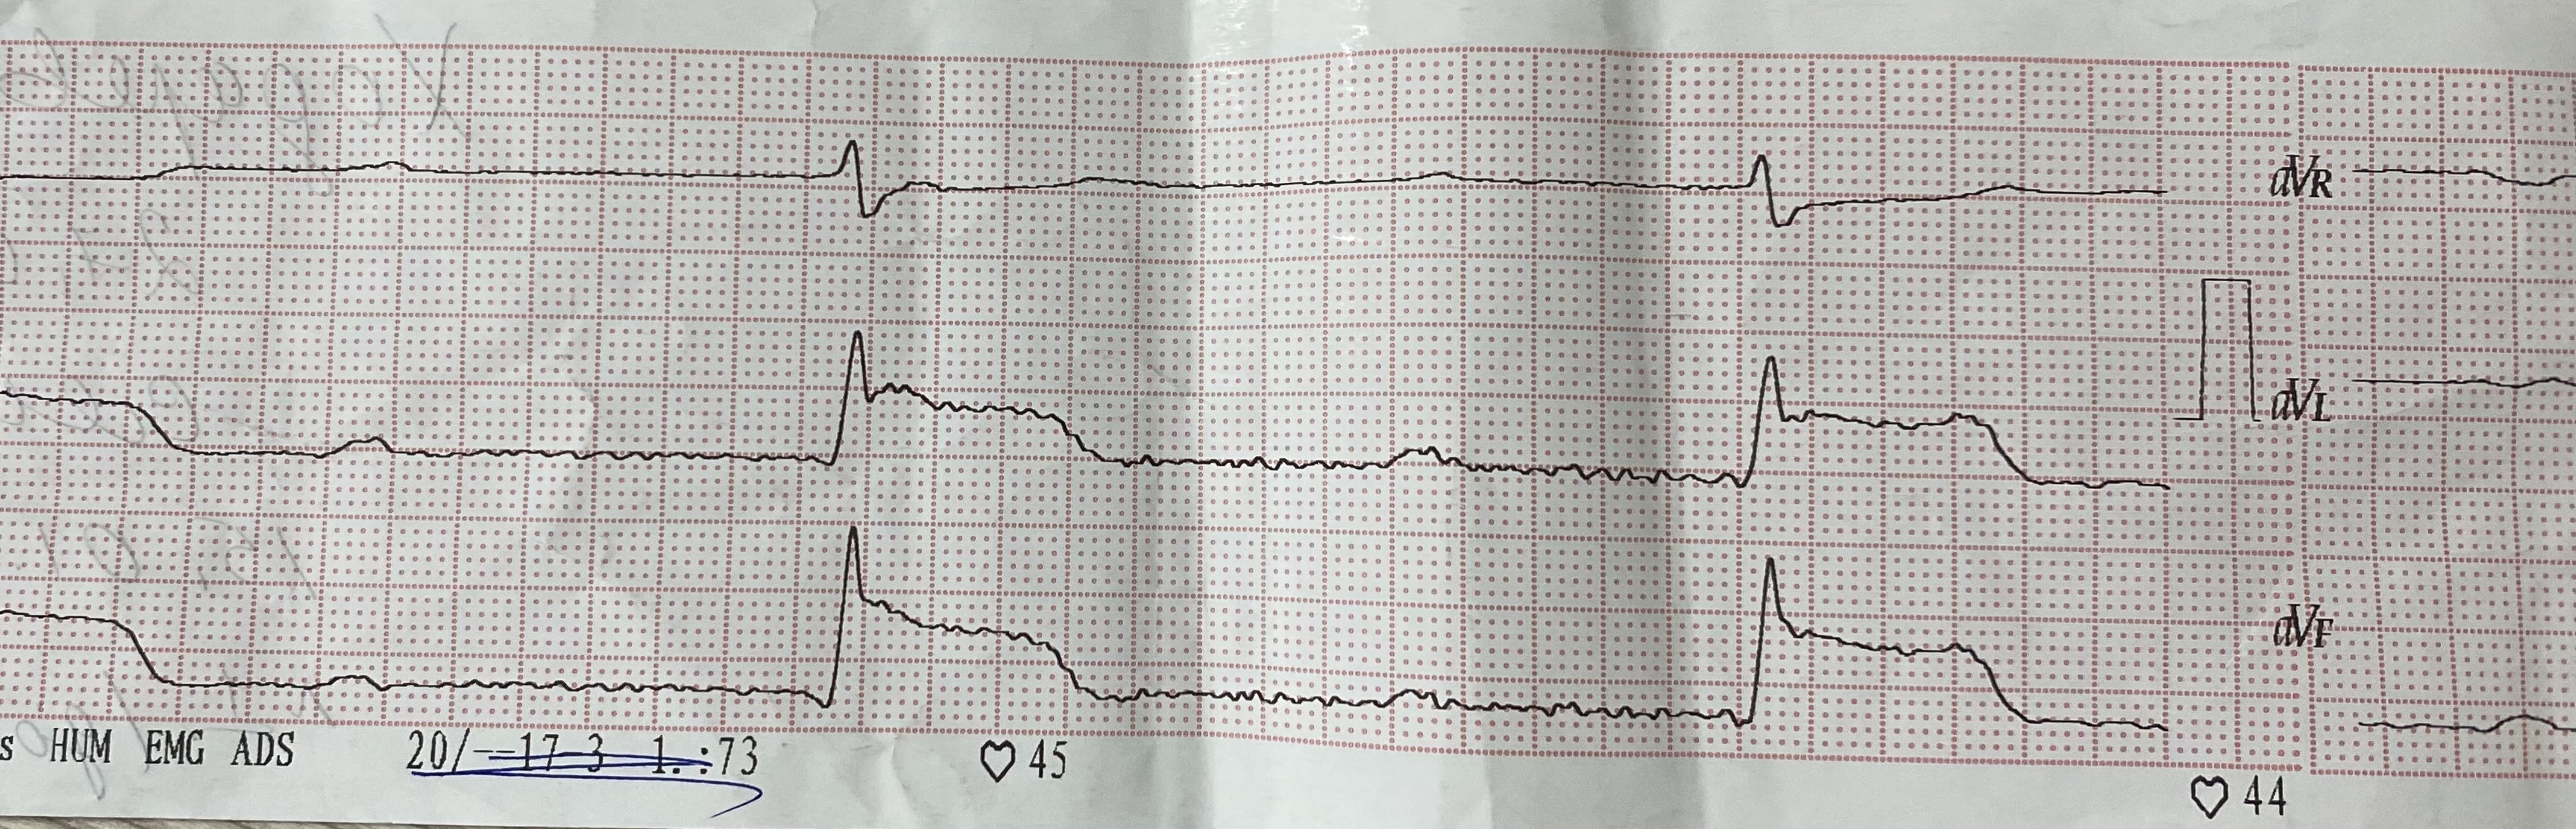

АВ бл 2 тип 2

Обсуждалось здесь https://vk.com/club84409679?w=wall-84409679_13522%2Fall